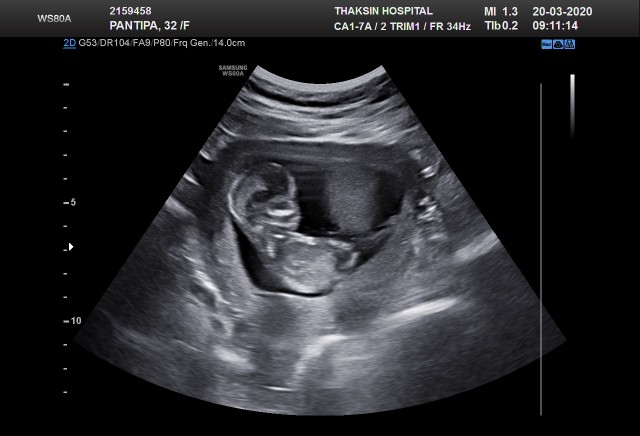

บ้านนี้ไม่ขึ้นเลยค่ะ แต่เน้นทานสารอาหารครบ ลูกตัวโตแข็งแรงดีค่ะ ภาพนี้ 13w+1

3เดือนกับ1อาทิตย์ แม่คนไหนรู้เพศเเล้วบ้าง เพิ่งไปซาวมาหมอเห็นเพศน้องเเล้วค่ะ